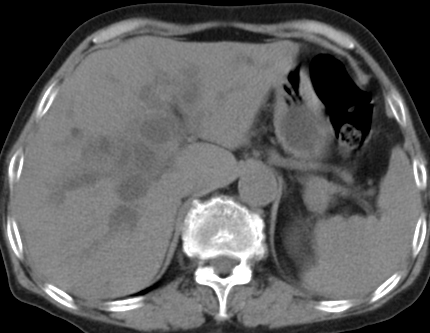

以下是引用齐原在2006-11-8 23:21:00的发言:[br]肝脏体积增大.肝表凸凹不平,肝内胆管扩张,胆总管扩张,胆总管末端突然截断,胰腺勾突增大,形态不规则.胰管扩张.考虑胰头癌.并低位梗阻性胆系扩张,胆囊炎.脾大.建议增强

以下是引用dyqct在2006-11-9 9:14:00的发言:[br]肝大,表面呈波浪状,肝内外胆管扩张,胆总管下端腔内见小结节状等密度影,胰管轻度扩张。胆囊显示不清。[br]考虑:1、胆总管下端占位性病变(等密度结石?壶腹部肿瘤?);[br] 2、肝硬化?[br] 3、建议增强扫描进一步检查。